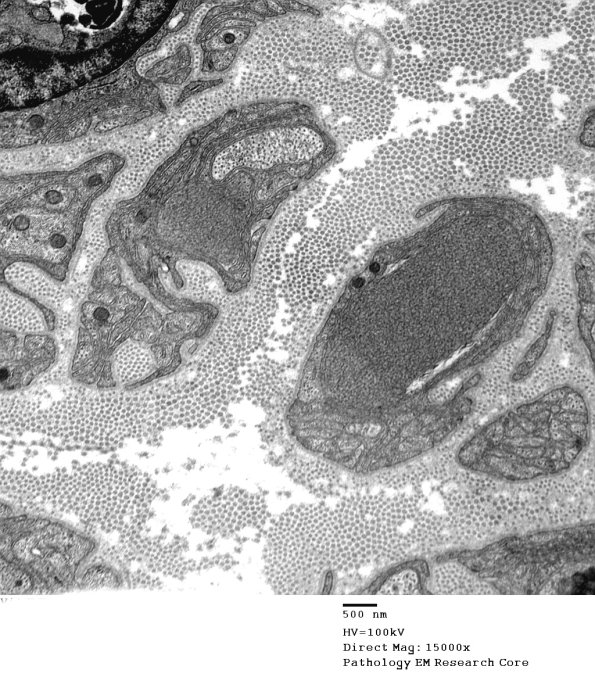

1B6A,B Multiple tubulovesicular elements are seen in two nearby dystrophic axons. In studies of the sympathetic nervous system of experimentally diabetic rats, near sequential sections show apparent dystrophic axonal splitting. (electron micrographs)